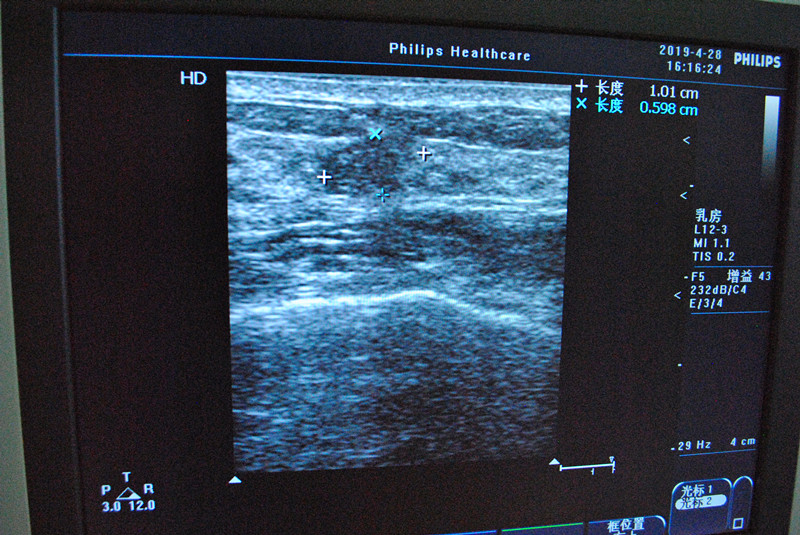

4月28日下午,我院外二科成功开展了3例乳腺微创旋切手术。该手术是利用彩超引导,借助目前先进的真空辅助微创旋切系统,在局部麻醉下通过一个仅约3-5毫米的皮肤切口将直径3cm以下的乳腺肿块完整地切除,切除组织送病理检查。整个手术过程严格遵循无菌操作规程,用时短,3名患者术后恢复良好,无不良反应,均高度满意。